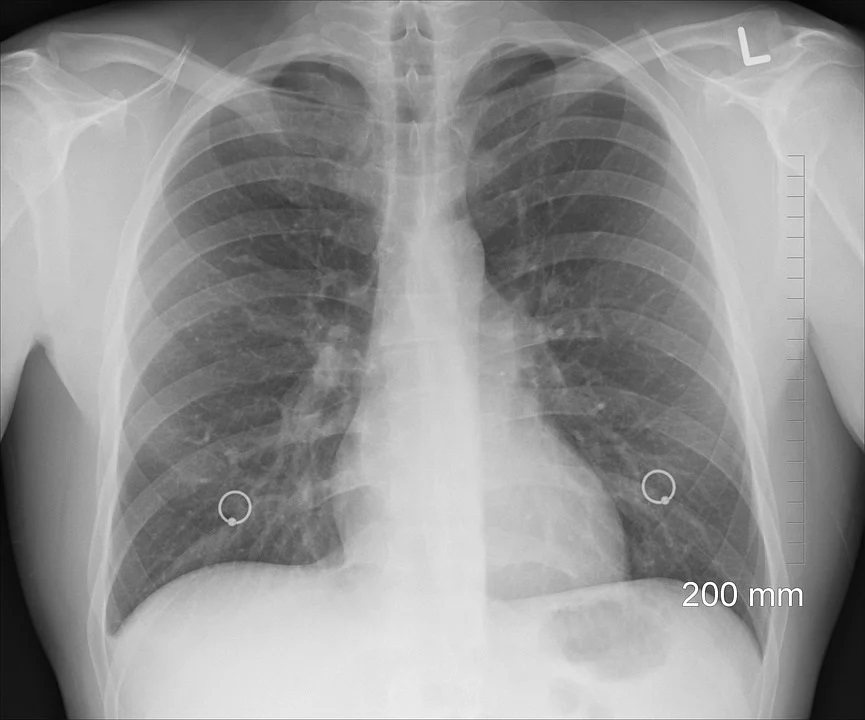

Právě kvůli souvislosti, propojení obou nemocí a jejich záludnosti v tom, že se zpočátku téměř nijak neprojevují, chtějí plicní lékaři v rámci unikátního národního screeningu rakoviny plic sledovat i CHOPN.

A právě takoví pacienti zároveň splňují podmínky vstupu do chystaného screeningového programu zaměřeného na časnou diagnostiku plicní rakoviny.

V praxi jde o to, že plicní lékař kromě cíleného pátrání po plicním nádoru jednorázově provede nebolestivé vyšetření plicních funkcí. Podle prof.

Od ledna startuje národní screening plic, kterým by měly projít desítky tisíc rizikových osob.